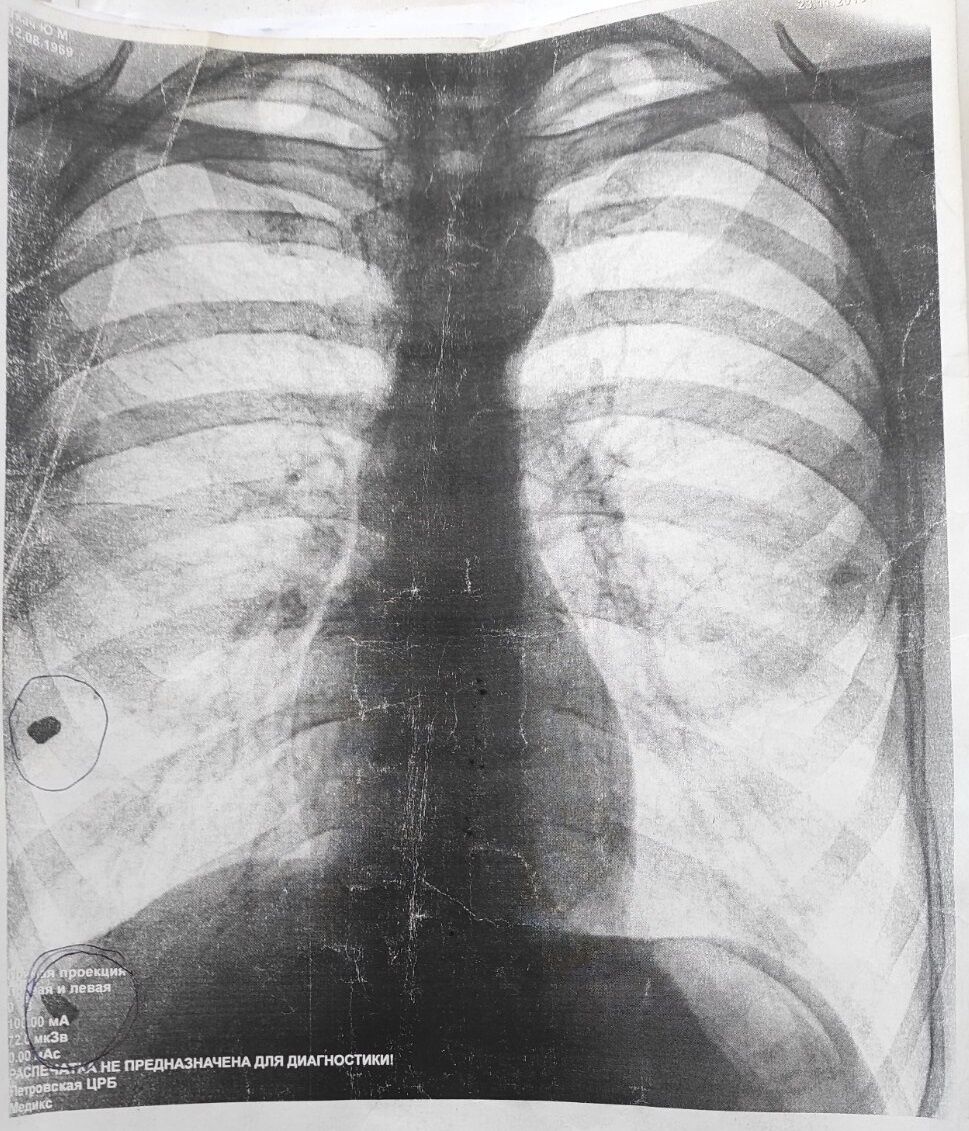

– Да. Из них два тяжелых. В 2010-м, 2013-м – насквозь в левую сторону груди, в 2014 году – тяжелое огнестрельное ранение. Мне не оказали помощь. Я пережил клиническую смерть и вытащили пулю, которая есть на снимке. На мои неоднократные обращения в прокуратуру – в областную, в райотдел, к следователям – до сих пор мне не предоставили направление на судебно-медицинскую экспертизу. Мне все отказывают.

– Да. В правом легком – на снимке видно, что они есть. В 2013 году то же самое было. Тот же Поворознюк. Они прошли насквозь – левую сторону. Есть справка из приемного отделения Петровской центральной больницы.